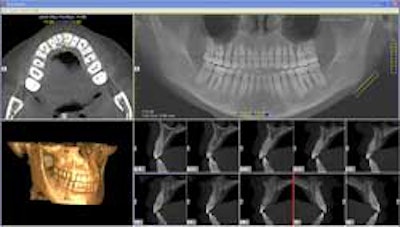

Cone-beam CT, on the other hand, provides important radiographic, restorative, and surgical information, including implant trajectory, distribution, depth, and proximity to critical anatomical landmarks, according to Allan Farman, B.D.S., M.B.A., Ph.D., D.Sc., a professor of radiology and imaging science at the University of Louisville in Kentucky and president of the American Academy of Oral and Maxillofacial Radiology (AAOMR).

Cone-beam CT provides important radiographic, restorative, and surgical information for implant treatment planning, including implant trajectory, distribution, depth, and proximity to critical anatomical landmarks. All images courtesy of Scott Ganz, D.M.D.